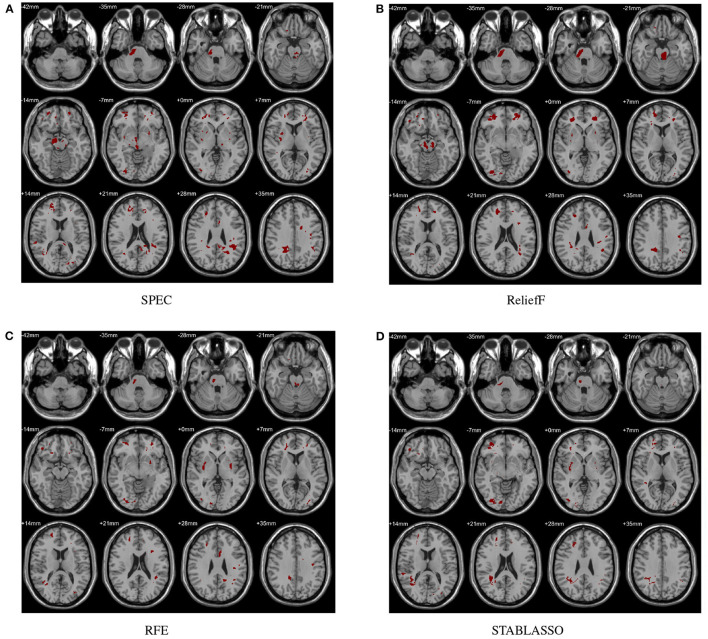

In this study, the abnormal brain regions have been illustrated in Figure 4 and reported based on AAL (Automated Anatomical Labeling atlas) with 116 brain regions (Tzourio-Mazoyer et al., 2002). We found that the SPEC method identified the largest number of features based on brain GM analysis, followed by ReliefF and RFE, and STABLASSO found the fewest, as seen in Supplementary Table S5. Furthermore, we note that the significant brain regions found by SPEC included all the brain regions found by the other three methods. The brain regions found commonly by all four methods included the PCUN, CAU, STG, MFG, MOG, MTG, INS, SFGdor, ORBinf, IPL, and ANG. Except SFGdor, other brain regions have been reported in the previous studies. Furthermore, the findings of statistical analysis on GM have been listed in Supplementary Table S3. It is easy to find that most brain regions found by statistical analysis also have been identified by machine learning methods, except CAL with the cluster size 113. The possible reason is that the cluster size is too small or the changes in this brain region is subtle.

Figure 4.

Biomarkers identified on GM by different methods. (A) Biomarkers identified by SPEC; (B) Biomarkers identified by ReliefF; (C) Biomarkers identified by RFE; (D) Biomarkers identified by STABLASSO.